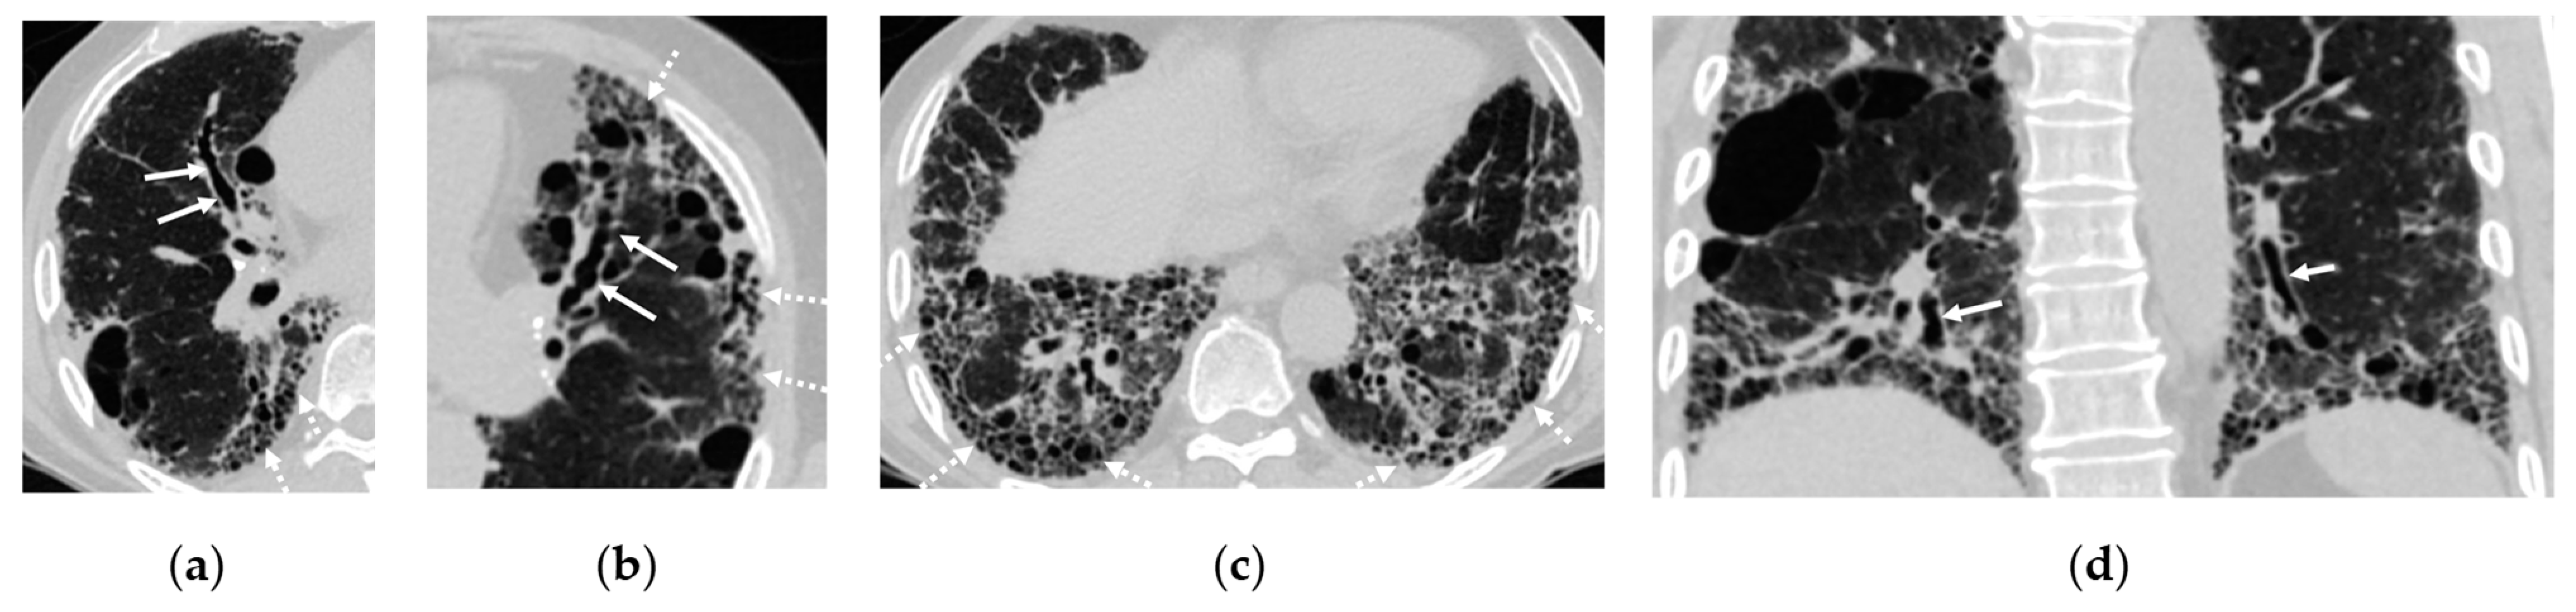

- Figure 2: The original figure intended to illustrate interstitial lung disease (ILD) but inadequately highlighted bronchiectasis in Figure 2a. Additionally, Figure 2b,c presented confusing representations with the consolidation in the right lower lobe. The revised figure now accurately showcases the full spectrum of ILD findings, including traction bronchiectasis, reticulations, cystic changes, and honeycombing. Furthermore, the citation for Figure 2 has been corrected to ensure relevance to the surrounding text.